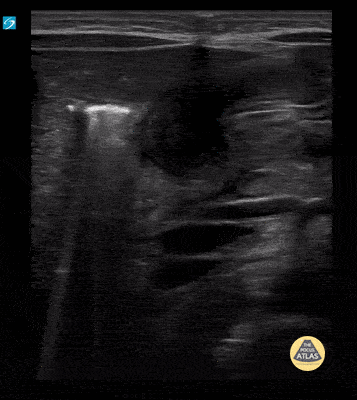

5 wk old male with projectile vomiting. Clips show hypertrophic pyloric stenosis in long axis. Contributor: Paul Khalil, MD Nicklaus Children's Hospital @khalil3paul